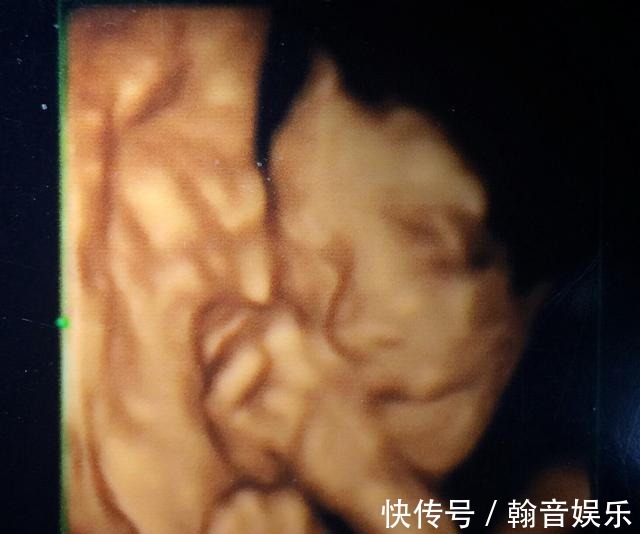

导读:关于四维彩超背后隐藏的误区和认识,准妈妈中招了吗?近年来,四维彩超开展得如火如荼,逐渐深入人心,但是很多孕妈妈对四维彩超在认识上还是有些误区,经常接到关于四维彩超的提问。

提问汇总1、四维彩超有必要做吗?2、四维彩超有辐射吗?3、四维彩超能查处唐氏儿吗?4、四维彩超查出有问题,胎儿就不能要了吗?5、四维彩超没看到耳朵怎么办?诸如此类问题,孕妈妈深感困惑,所以,今天就来说一说孕妈妈常常关心的一些问题,消除孕妈妈的困惑。